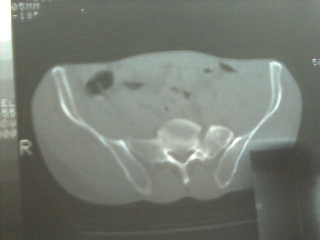

以下是引用sdqzwyx在2006-12-6 13:22:00的发言:[br]图片不全,考虑腰5不完全骶化(腰5左侧横突肥大与骶骨形成关节),定位像应该很明确的。

以下是引用乡医在2006-12-6 14:55:00的发言:[br]腰5左侧横突肥大,属发育变异。

以下是引用一棵树在2006-12-6 13:13:00的发言:[br]腰5左侧横突肥大(比较常见)